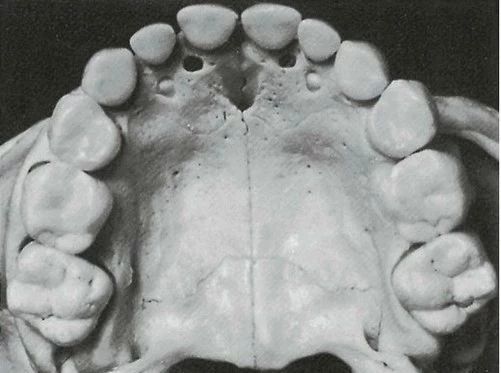

别以为只是自己的门牙大所导致的,它是东亚人有别于其他区别地区人种的显著生理特征。这个特征它有一个较为专业的名称叫做铲型门齿,指的是在我们上颌两颗中门齿的两边缘翻卷成棱,中间低凹,会像一把铲子。

在我国绝大多数人都是这种门齿,铲形门齿有的还会延伸到唇侧面,使门齿的唇侧面中央凹陷,形成双铲形门齿。在东亚人中,铲形门齿出现的比例约为90%,而欧美人和非洲人铲形门齿的出现率极低。

铲形门齿

普通牙齿

铲形门齿分级